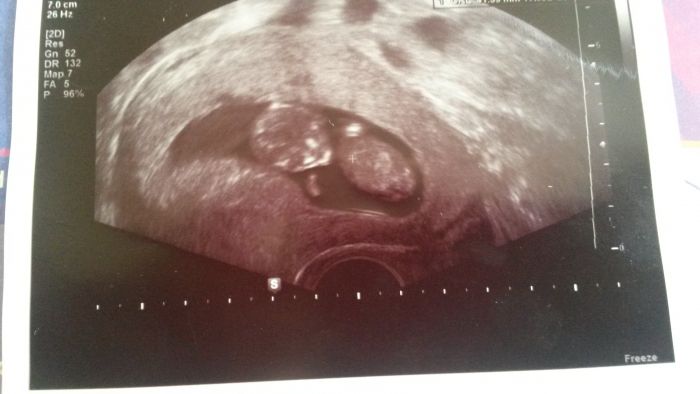

Ahoj holky zdravím všechny. Jdu se taky pochlubit. Máme prý 7 cm už a termíny mam pro jistotu dva dle ms 27.12 a dle utz 29.12 tak to budou svátky a dcera má 30.12 narozky. Jinak vse v poho a na konci měsíce se dozvím co to bude. Přidám foto. Tak zatím a všem držím pěsti.